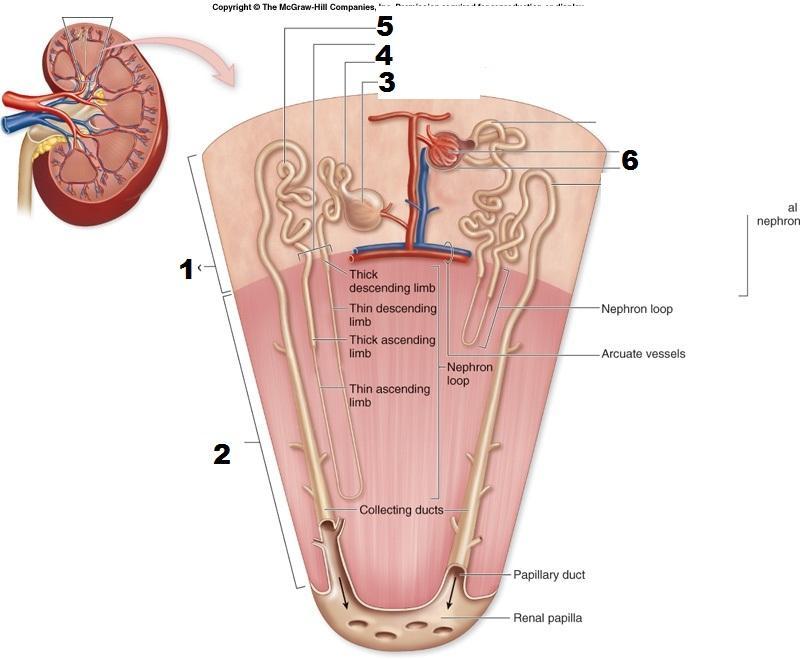

Afferent/efferent arteriole

Calyx (of the kidney)

Collecting duct

Descending/Ascending loop (of nephron)

Distal (convoluted) tubule

Glomerular capsule (=Bowman's capsule)

Glomerulus (=glomerular capillaries)

Juxtaglomerular apparatus

Medullary pyramids

Nephron

Peritubular capillaries

Proximal (convoluted) tubule

Renal artery/vein

Renal capsule

Renal columns

Renal corpuscle

Renal cortex

Renal medulla

Renal Pelvis